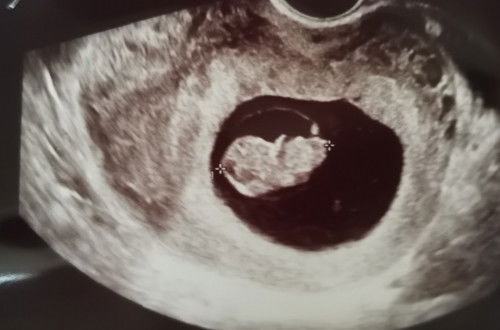

อายุครรภ์ 9 wk. ความยาวน้อง 2.3 cm.อยู่ในเกณฑ์ปกติไหมคะ

ท้องแรกค่ะ ตอนนี้อายุครรภ์ 9 สัปดาห์ คุณหมอแจ้งว่าความยาวน้องอยู่ที่ 2.3 ซม อยู่ในเกณฑ์ปกติไหมคะ จากรูป ฝั่งไหนคือทางหัว หรือทางขาหรอคะ แม่ๆช่วยบอกทีนะคะ #ขอบคุณล่วงหน้านะคะ